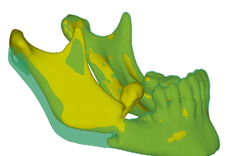

- Dzięki zastosowaniu modeli żuchwy wykonanych przy użyciu druku 3D, znacznie skrócono czas przeprowadzenia zabiegu chirurgicznego, a także zminimalizowano wystąpienie komplikacji śródoperacyjnych - wyjaśnia twórca modelu dr inż. Paweł Turek, adiunkt w Katedrze Technik Wytwarzania i Automatyzacji PRz. - Dodatkowo opracowano procedurę umożliwiającą komputerowe (wirtualne) odtworzenie geometrii żuchwy sprzed wystąpienia urazu.